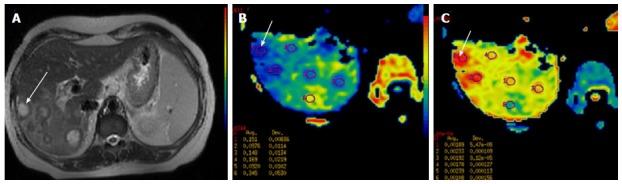

"Personalized oncology" is a multi-disciplinary science, which requires inputs from various streams for optimal patient management. Humongous progress in the treatment modalities available and the increasing need to provide functional information in addition to the morphological data; has led to leaping progress in the field of imaging. Magnetic resonance imaging has undergone tremendous progress with various newer MR techniques providing vital functional information and is becoming the cornerstone of "radiomics/radiogenomics". Diffusion-weighted imaging is one such technique which capitalizes on the tendency of water protons to diffuse randomly in a given system. This technique has revolutionized oncological imaging, by giving vital qualitative and quantitative information regarding tumor biology which helps in detection, characterization and post treatment surveillance of the lesions and challenging the notion that "one size fits all". It has been applied at various sites with different clinical experience. We hereby present a brief review of this novel functional imaging tool, with its application in "personalized oncology".

“个性化肿瘤学”是一门多学科科学,为实现最佳的患者管理,需要各个领域的投入。现有治疗方式取得了巨大进展,除形态学数据外,提供功能信息的需求也日益增加,这推动了成像领域的飞跃发展。磁共振成像随着各种更新的磁共振技术取得了巨大进步,这些技术提供了至关重要的功能信息,并正成为“放射组学/放射基因组学”的基石。扩散加权成像就是这样一种技术,它利用了水质子在给定系统中随机扩散的趋势。这项技术通过提供有关肿瘤生物学的重要定性和定量信息,彻底改变了肿瘤成像,有助于病变的检测、特征描述和治疗后监测,挑战了“一刀切”的观念。它已在不同部位应用,并积累了不同的临床经验。在此,我们简要综述这一新型功能成像工具及其在“个性化肿瘤学”中的应用。